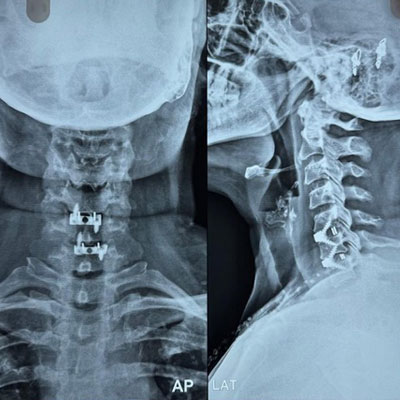

Dr. Ujwal Yeole is an experienced neurosurgeon specializes in treating a wide spectrum of neurological conditions including neuro-oncology, peripheral nerve disorders, vascular disorders, spinal pathologies, pediatric neurosurgery, neuro-trauma and skull base neuroendoscopic procedures.